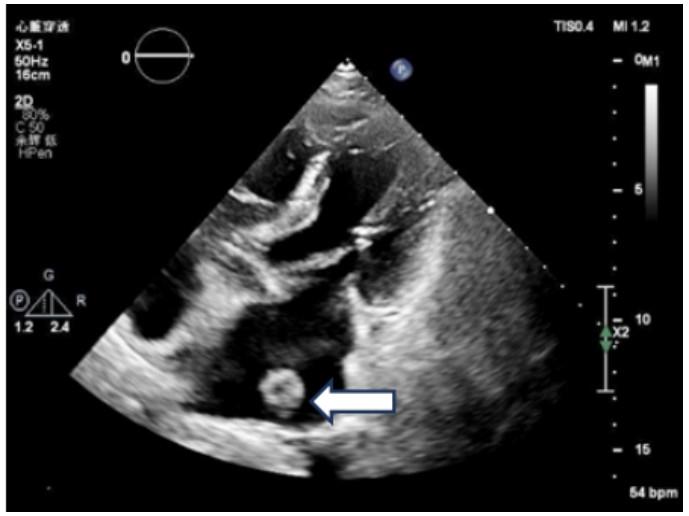

既往史:有高血压病史10年余,规律降压治疗,未监测血压。房颤病史2年余,2022年11月在本院超声心动图显示左心房见一不均质低回声团,位置随心动周期漂动(17 mm×16 mm)”(见图 1),左房前后径40 mm,左右径46 mm,上下径70 mm。LVEDD 39 mm,LVEF:60%。二尖瓣E峰0.92 m/s,最大压差3.39 mmHg(1 mmHg=0.133 kPa)。反流面积3.8 cm2,二尖瓣口频谱呈单峰。舒张期二尖瓣口前向血流,E < A,无舒张功能不全。进一步行经心脏超声造影提示:Flash后,左心室心腔内团块未见明显灌注(见图 2)。

注:左房内可见团块样回声影(箭头处),约17 mm × 16 mm 图 1 患者经胸腔超声心动图